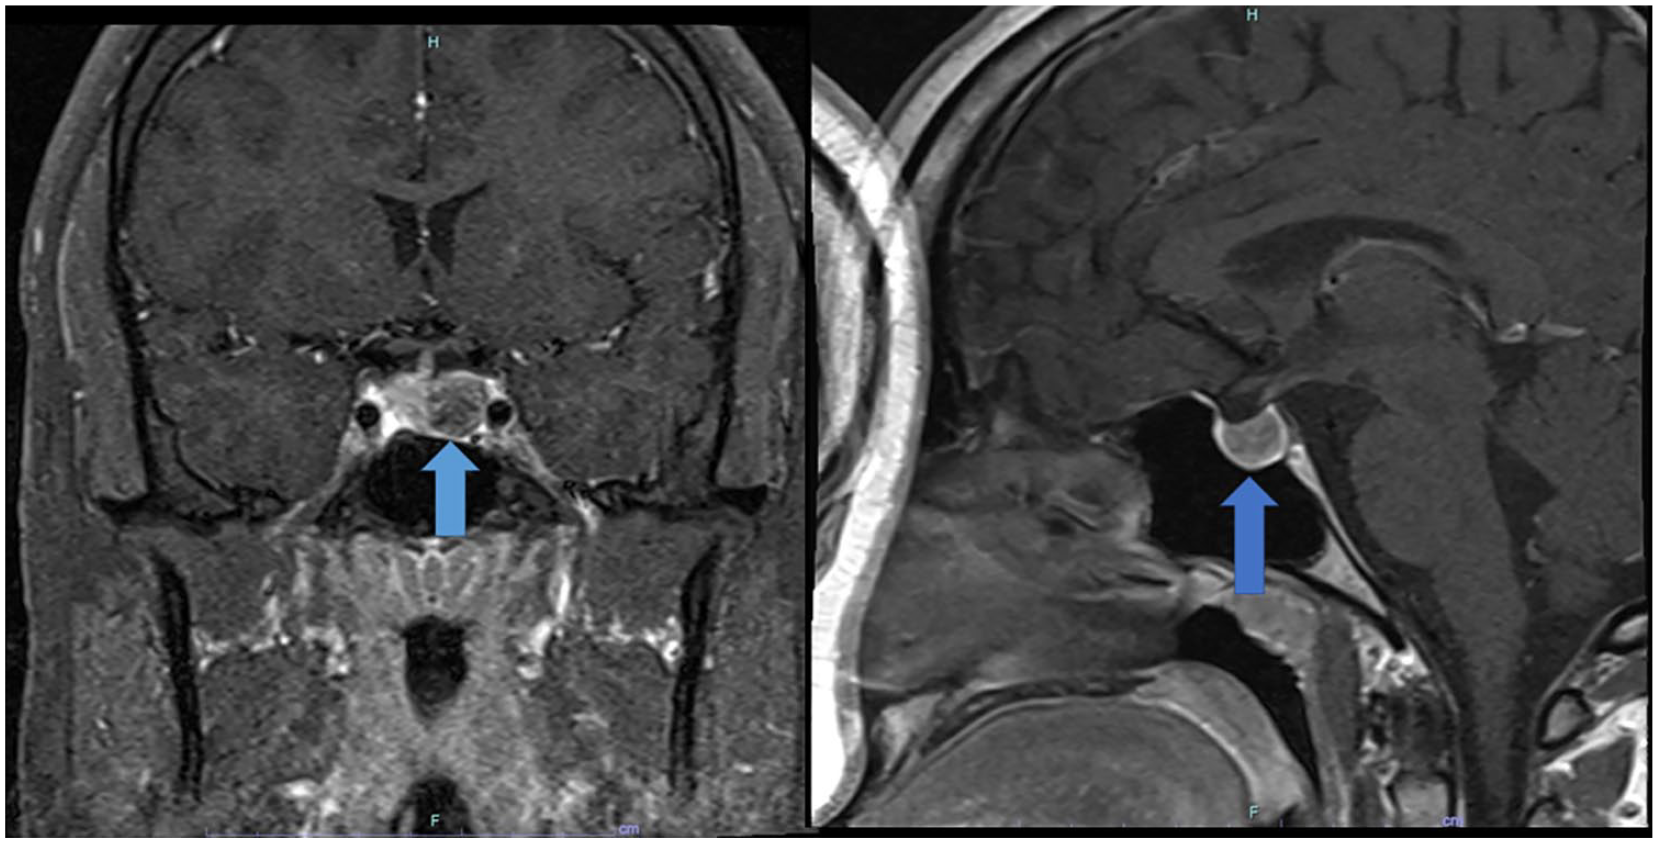

A 20-year-old African American man was diagnosed with a macroprolactinoma after presenting to his primary care physician with complaints of worsening headaches, erectile dysfunction, gynecomastia, and nipple discharge for the past 6 months. Initial investigation revealed an elevated prolactin level of 550.8 ng/mL (reference range = 2.0-18.0). He also had hypogonadotropic hypogonadism with a low total testosterone of 26 ng/dL (250-11 000) and inappropriately normal luteininzing hormone level of 1.6 mIU/mL (1.6-9.3) and follicle-stimulating hormone level of 2.3 mIU/mL (1.6-8.0). The rest of the pituitary axis was normal (Table 1). A pituitary protocol magnetic resonance imaging study (MRI) showed a 17 mm × 12 mm pituitary gland adenoma with extension into the medial aspect of the left cavernous sinus, with rightward displacement of infundibulum (Figure 1). A visual field examination interpreted by a neuro-ophthalmologist did not reveal any deficits.

Magnetic resonance imaging images of the pituitary adenoma at diagnosis.